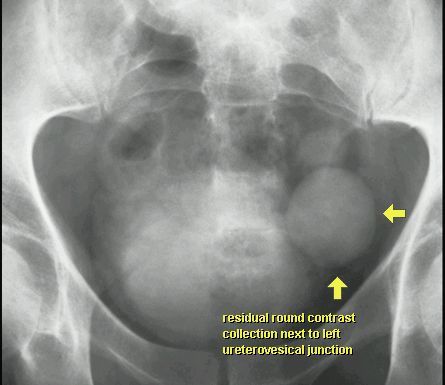

RTG

UCHYŁEK PĘCHERZA MOCZOWEGO

UROGRAFIA